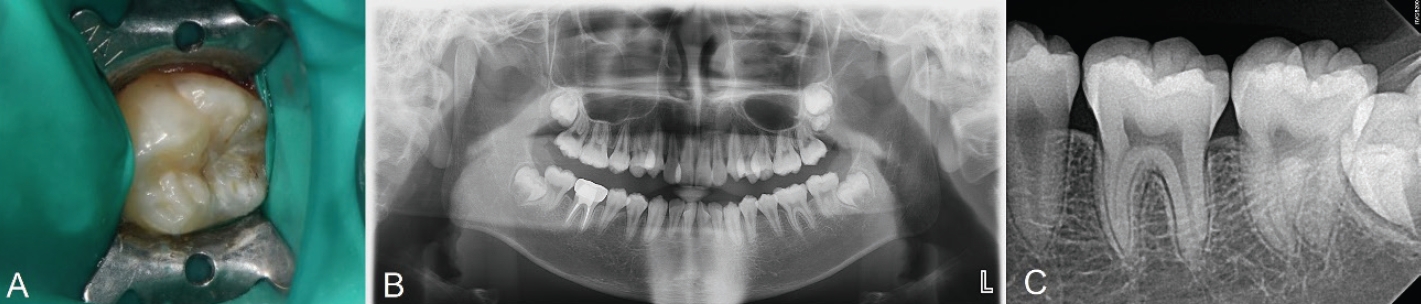

13세 여성 환자가 부산대학교치과병원 치과보존과에 좌측 하악 구치부 우식을 주소로 내원하였다. 환자의 전신 병력 및 치과 병력 특이사항은 없었다. 구내 검사에서는 좌측 하악 제2대구치에서 치면열구 우식이 관찰되었다. 교합면 형태는 보존되어 있었고, 명확한 공동(cavitation)은 관찰되지 않았다(Fig. 3A). 원심 및 설측 교합면 일부가 미맹출하여 치은판개에 덮여 있었다. 냉자극과 온자극에 대한 반응은 정상적이었다. 타진이나 저작에 대한 통증도 없었다. 파노라마 및 구내 치근단 방사선사진 상 상아질까지 진행된 깊은 우식을 관찰할 수 있었다(Figs. 3B and C). 이 결과를 바탕으로 우식 부위를 복합레진으로 수복하면서 스탬프 테크닉을 적용하기로 결정하였다.

Initial examination radiograph and clinical photograph. A. No loss of tooth structure was observed. B. Preoperative panoramic radiograph. C. Caries of dentin is seen on olwer left second molar.